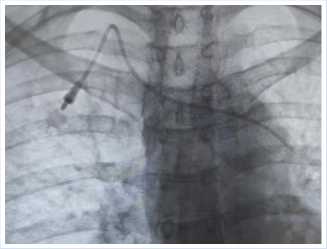

Протокол операции. Под местной анестезией и ультразвуковым контролем была пунктирована правая внутренняя ярёмная, через пункционную иглу был проведен диагностический проводник. После рентген контроля было выявлено, что проводник располагается левее трахеи и левого бронха. Была несколько раз проведена попытка переустановить проводник, однако его положение не менялось (Рис. 1).

Рис. 1. Рентгенограмма проведения диагностического проводника.